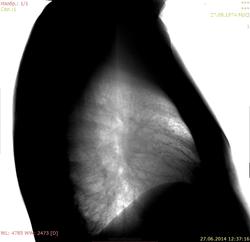

Да. здесь застой.

Написал бы: сердце митральной конфигурации, корни расширены, легочный рисунок диффузно обогащён. (Может ещё кто добавит симптом "крыльев бабочки"? )

Нее...,про "бабочку" молчим, она "из саркоидоза".

Бабочка - это отек легких.

А почему здесь не диссеминация?

Ну, бабочка при многих нозологиях летает, коллагенозы тоже любит (СКВ, например). Конкретно к этому больному-проблемы застойного характера есть, конечно, кардиологу надо показать. Но в 40 лет уж больно избыточен легочный рисунок. Смущает и одышка( может, и сердечной этиологии быть) .Итак, диф. ряд-сердечные дела, саркоидоз, ИФА.Я бы проКаТила, но это -по возможности.Зато сразу-причина такого рисунка ясна была бы. Кстати, а профессия какая у пациента?